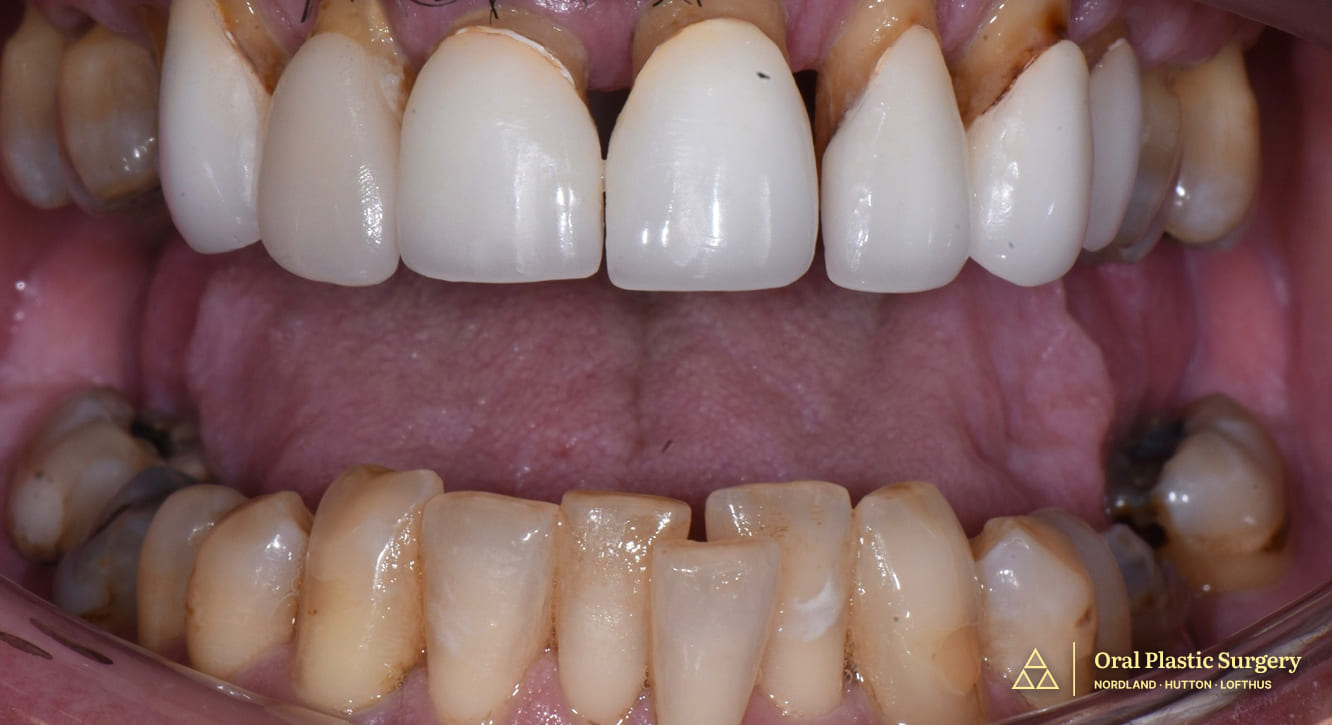

Phil had battled advanced periodontal disease and failing teeth for years.

His smile was unsightly, his teeth were loose, and chewing most foods was nearly impossible.

Chronic infections and pain were a constant burden.

As a national public advocate and speaker, Phil felt ashamed of his smile and knew he was living on borrowed time with his failing teeth.

A full smile transformation: loose, painful teeth were removed and replaced with a stable, implant-supported restoration.